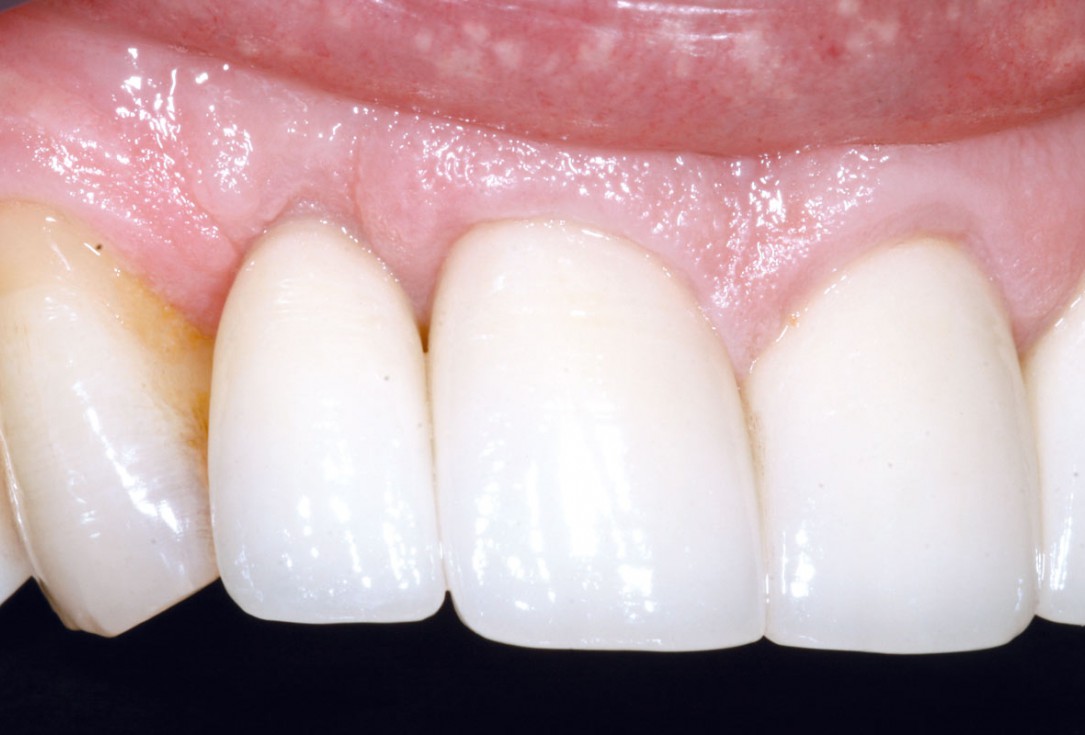

1/19 - Initial situation: Inflammated tooth #12Bone augementation with maxresorb® - Dr. R. Cutts